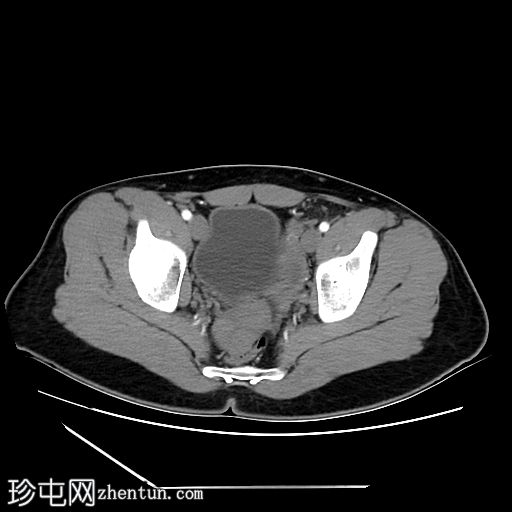

CT

轴位

平扫

1.jpg

阴茎:发育良好。阴茎海绵体和尿道海绵体均存在。

阴囊:双侧均存在,但空虚。

左侧腹股沟深环可见一裂隙,大网膜脂肪由此突出至左侧阴囊。裂隙大小约20毫米。

盆腔左侧可见一形态良好的子宫样结构(57 x 17毫米),开口于前列腺尿道。

右侧睾丸位于盆腔右侧,膀胱与直肠之间。大小:56 x 29 毫米。

左侧睾丸位于盆腔中线左侧,膀胱上方,子宫底旁。该结构附着于从左侧腹股沟管延伸出的索状结构上。大小:38 x 22 毫米。

患者有双侧隐睾病史。CT和MRI图像显示发育良好的子宫和两个睾丸,均位于盆腔内。子宫内膜腔开口于前列腺尿道。